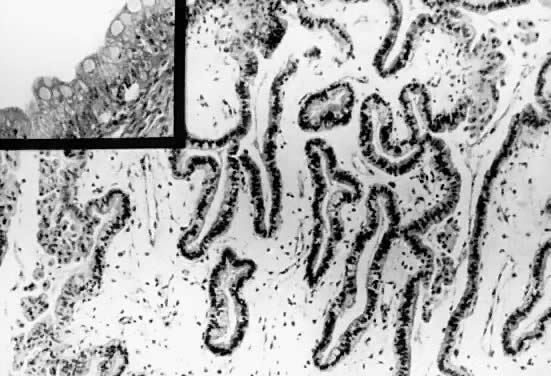

On microscopic examination, the LMP serous tumors are characterized by the presence of simple or complex, broad and fine papillary structures (Fig. 6). They have a distinctive fibrovascular core covered by different types of columnar epithelia with atypical nuclei and tufting. The papillary structures may occur on the external surface in approximately 50% of the stage I tumors (see Fig. 5). Notice that the surface excrescences are the result of tumor growing from the surface epithelium concomitantly with the excrescences in the lumen of the cyst. The excrescences on the external surface do not signify that the tumor has penetrated the wall of the cyst. In few cases, the papillary excrescences represent the only tumor present in the ovary.17,18

Fig. 6. Photomicrograph of a serous cystadenoma of low malignant potential. The tumor is composed mainly of papillary structures of different sizes resting on stroma made up of fibrous tissue. Tufting is observed in the interpapillary space (100).

Epithelial cells devoid of connective tissue detach, fall, and form rosette-like structures that float in the cystic fluid; this phenomenon is designated as tufting (Figs. 7 and 8). Hyalinization of the connective tissue of the papillary structures is seen more often in the LMP serous tumors than in serous cystadenomas.19 Papillae undergoing ischemic changes show edema and frequently slight acute inflammation of the stroma. In more advanced cases, frank necrosis may be evident.

Fig. 7. Inner lining of a serous cystadenoma of low malignant potential showing papillations with epithelial pluristratification, hyperchromasia, and tufting; there is some degree of nuclear atypia (420).